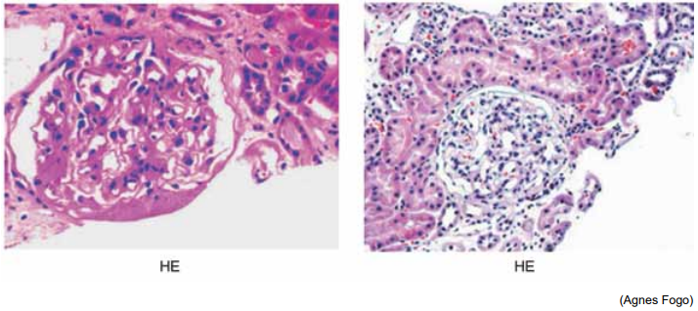

Observe a figura a seguir, na qual a microscopia óptica representa nefrite lúpica e sua classificação de acordo com

ISN/RPS (International Society of Nephrology e Renal Pathology Society):

Com base nesse contexto, qual o tratamento preconizado na fase de indução?